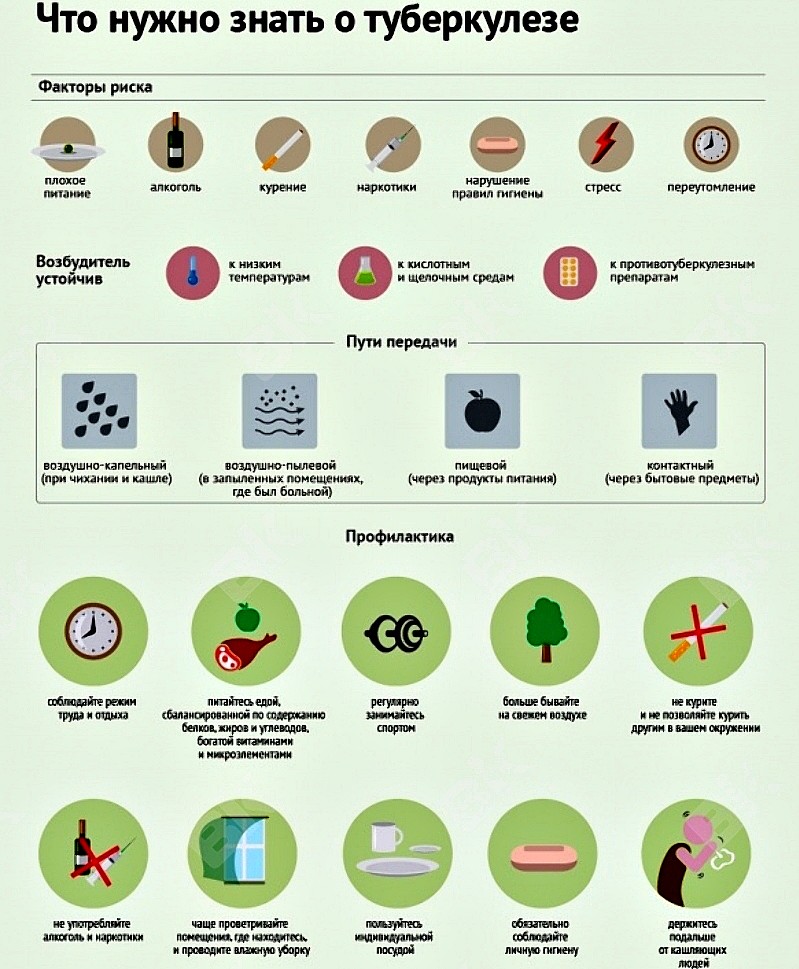

Факторами риска у взрослых людей являются хронические заболевания (органов дыхания, желудка, кишечника), длительный приём глюкокортикоидов, ВИЧ-инфекции, длительное белковое и жировое голодание, склонность к вредным привычкам (наркотики, спиртное, табак), нахождение в скученных коллективах (на работе, в армейской казарме, тюрьме), контакт с заболевшим человеком.

Основными симптомами заболевания являются: кашель более 2 недель, повышенная температура тела более 7 дней, затрудненное дыхание, боль в груди, плохой аппетит, постоянная слабость, беспричинная потеря веса, повышенная потливость, особенно ночью, кровь в мокроте, выделяемая при кашле.

Развитие болезни зависит от уровня иммунитета, поэтому основной профилактикой является ведение здорового образа жизни. Вакцинация детей, регулярные пробы и тесты, позволяющие выявлять заболевание на ранних стадиях, когда прогноз на лечение наиболее благоприятен, также играют значительную роль в профилактике заболевания.